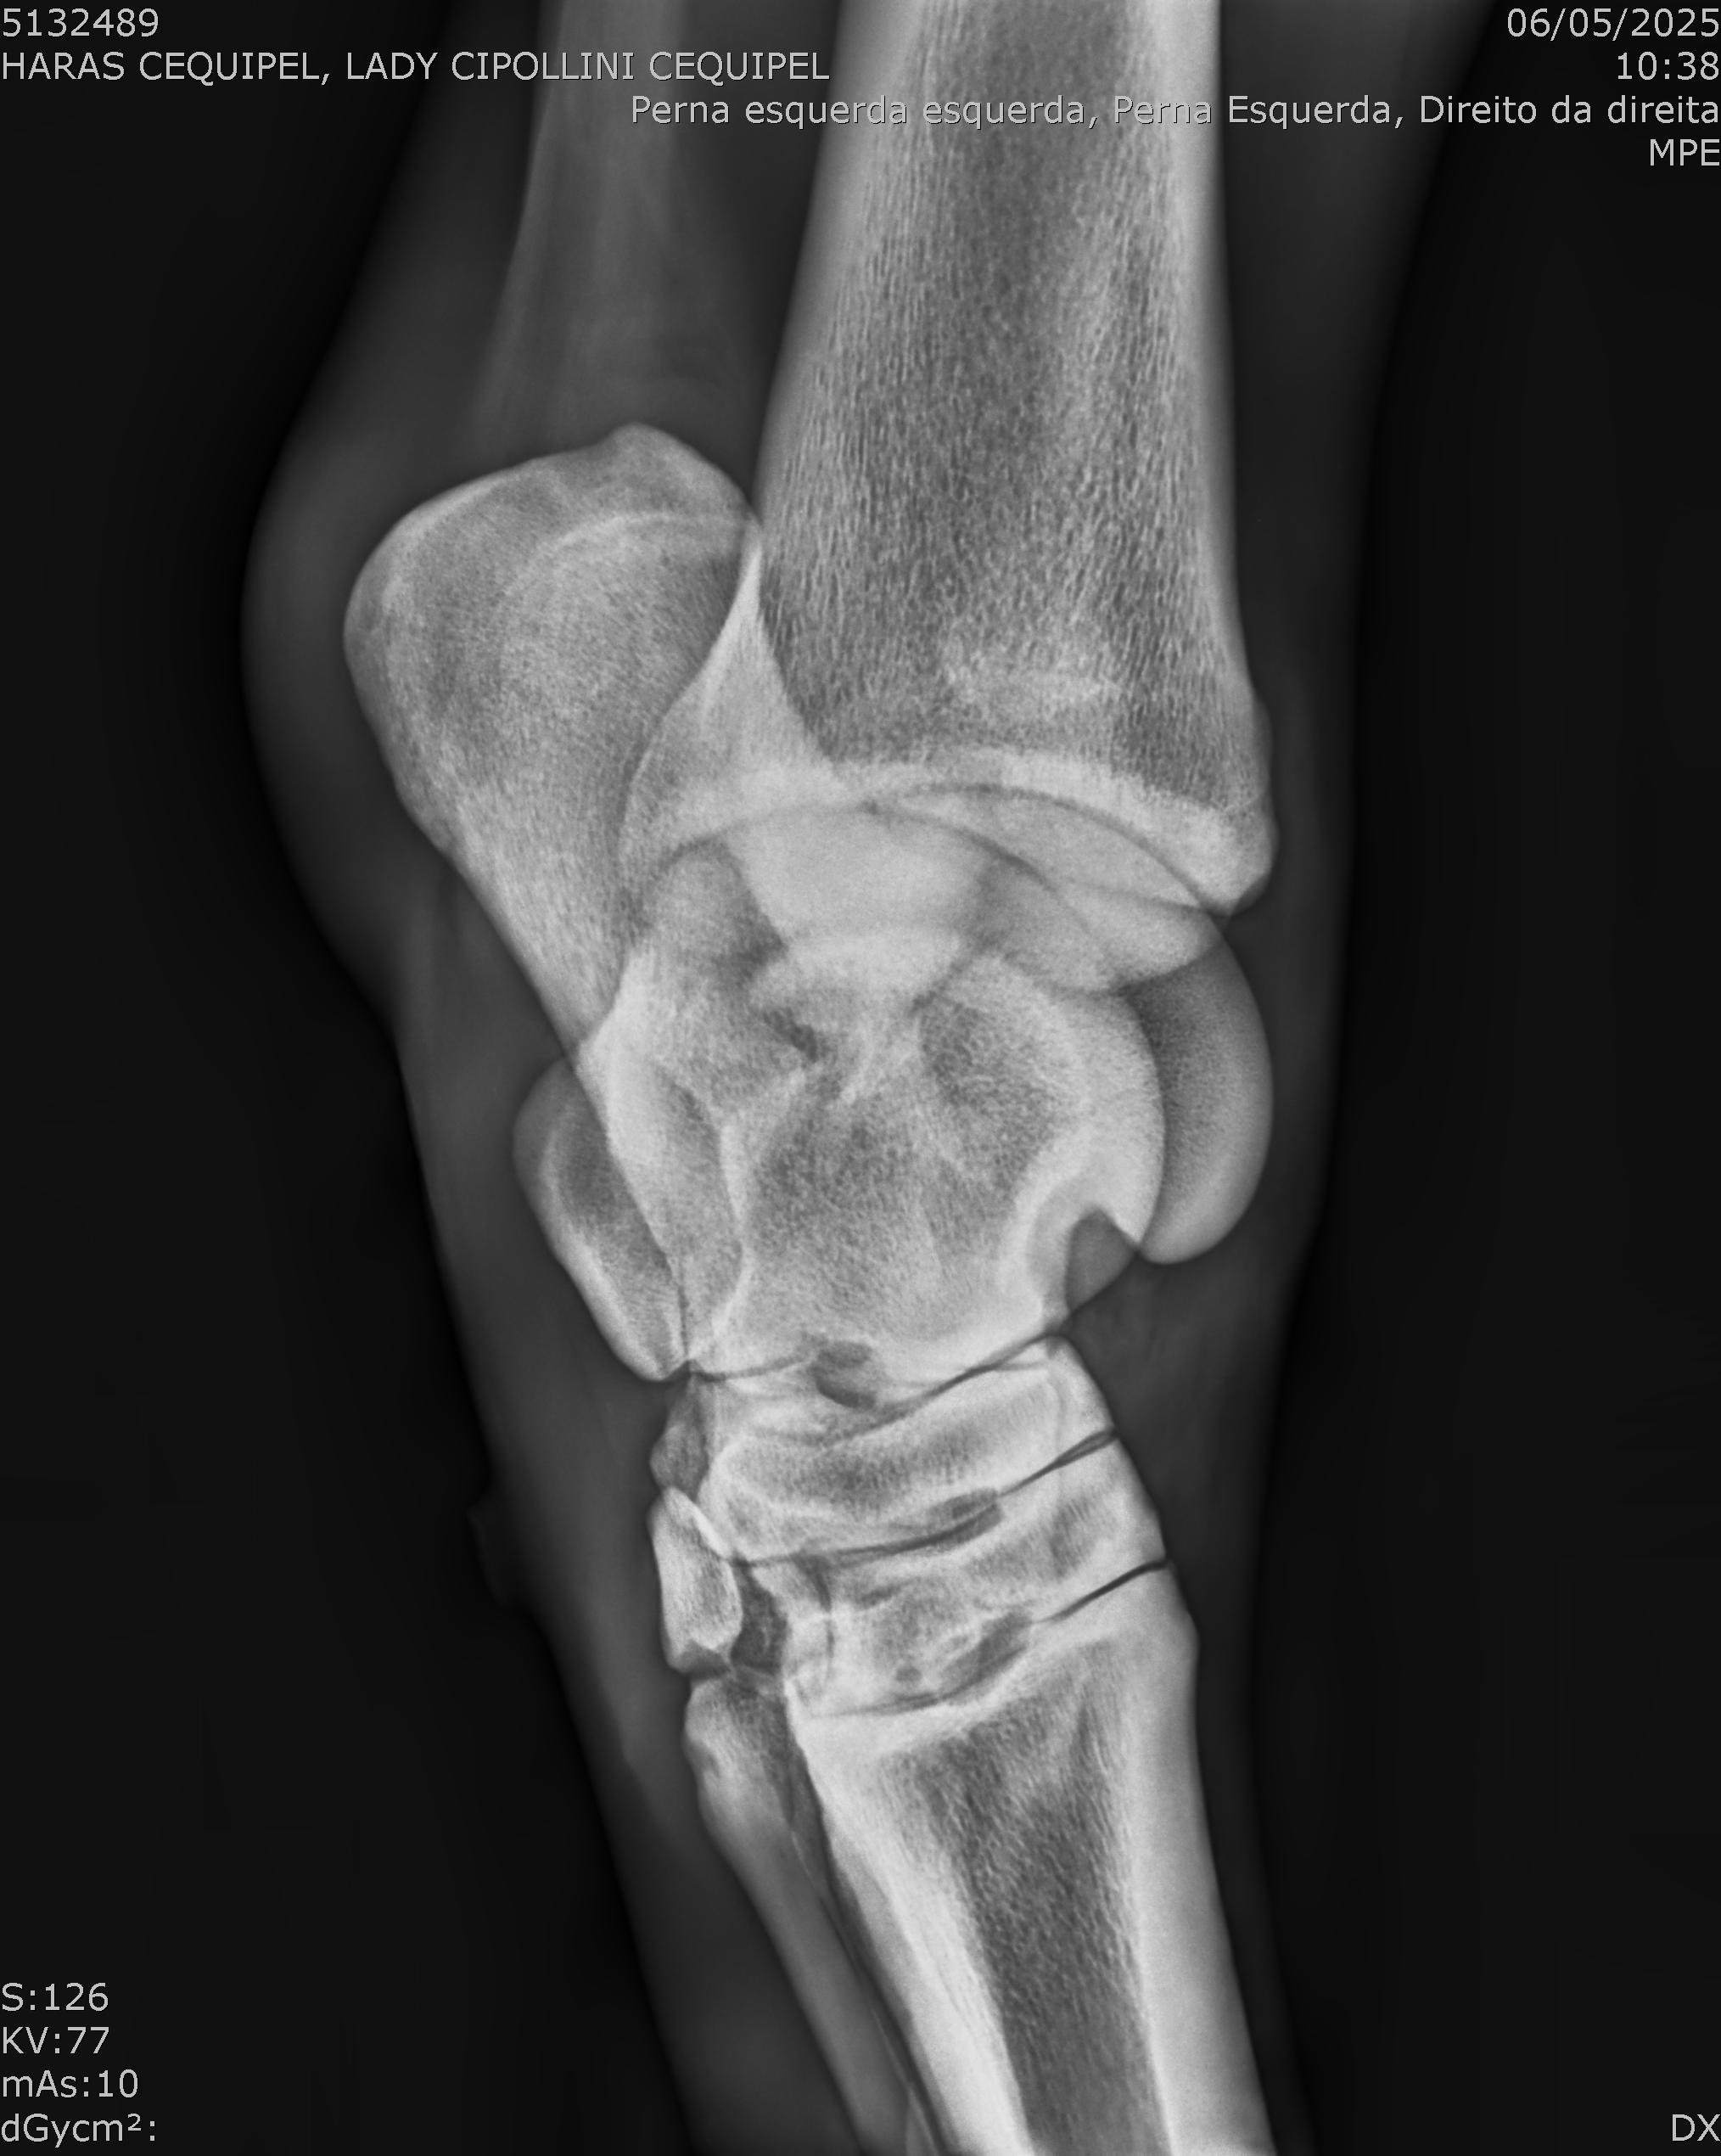

:: RAIOS-X DO LOTE